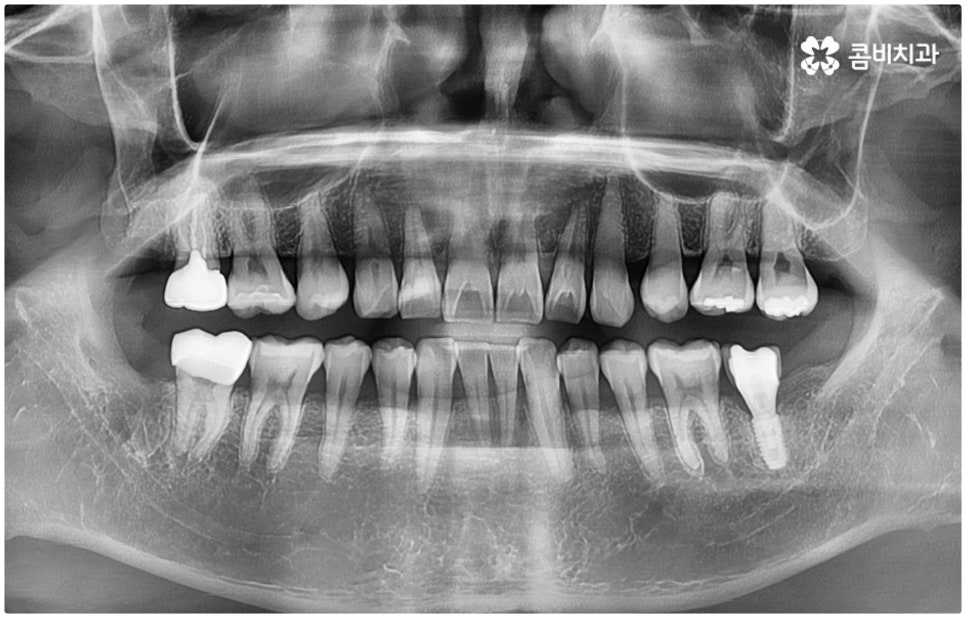

특히 매복 사랑니 중 잇몸 속에 전부 묻혀 있는 사랑니를 완전매복사랑니라고 부르는데 이 경우 누운 방향으로 자라나면서 앞 어금니 뿌리에 지속적인 압박을 가하여 신경을 누르기도 하고 치근을 흡수시키거나 치열이 앞쪽으로 쓰러지게 만들어 부정교합을 유발하기도 하며 드물게는 함치성 낭종이 생겨 턱뼈를 녹이는 상황까지 발생할 수도 있기 때문에 꼼꼼하게 검진을 하여 만약에 필요하다면 늦지 않게 발치 처치를 해 주어야 하는 거예요.

매복사랑니발치치과 를 선택할 때 어떤 것을 기준으로 고르는 것이 좋을까요? 사랑니가 완전히 매복되어 있다면 잇몸을 절개하고 상황에 따라 골삭제 후 치아를 조각내어 빼내줄 필요가 있는데 이러한 과정이 굉장히 까다롭기 때문에 먼저 환자분들의 사랑니 위치 및 뿌리의 형태, 인접 치아 구조, 주변 조직이나 신경 위치 등을 구체적으로 확인할 수 있는 3D CT와 같은 정밀 검진 장비를 갖추고 있는 매복사랑니발치치과 인지 체크해 보실 필요가 있어요.

하악 사랑니의 경우 하치조 신경을 건드리지 않도록 주의해야 하고 상악 사랑니의 경우 상악동 천공을 조심해야 하는데 이 때 환자분들의 상황 또한 개인마다 천차만별인 만큼 각각을 꼼꼼하게 살펴보고 섬세하게 발치 처치를 하기 위해 술자의 뛰어난 기술력 및 숙련도가 요구되므로 매복사랑니발치치과 의료진의 경력 사항을 면밀하게 살펴보시는 것도 도움이 될 거예요.